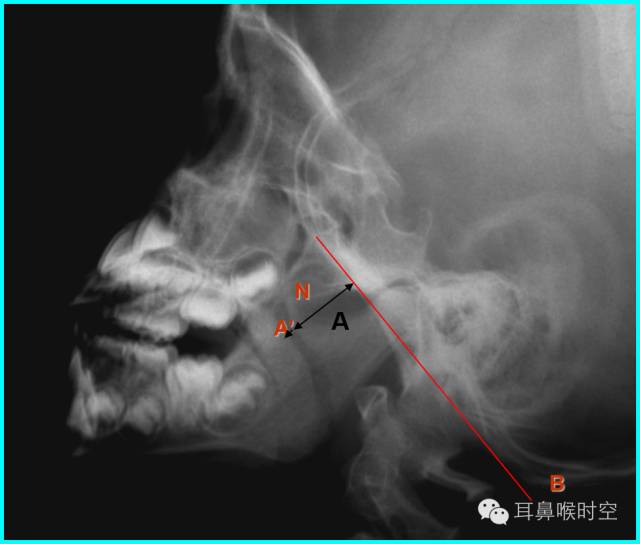

鼻咽侧位片的测量方法(一)

腺样体厚度(A)的测量:

测量:腺样体最突点至枕骨斜坡颅骨外侧面的垂直距离为腺样体厚度:

意义:>13mm,就会出现鼻咽腔气道变窄,甚至闭塞。

鼻咽侧位片的测量方法(二)

腺样体-鼻咽腔比率A/N值:

(1)1987年Elwany提出鼻咽腔的宽度(N)测量方法:

硬腭后端至翼板与颅底交点间的距离为鼻咽腔的宽度。

(2)现多用的鼻咽腔的宽度(N)测量方法:

N为腺样体最凸部鼻咽腔的宽度,即垂线的反向延长线与硬腭后端或软腭前中部上缘的交点和枕骨斜坡颅外面切线的垂直距离。

鼻咽侧位片的测量方法(三)

鼻咽后气道宽度(PAS)

PAS宽度:软腭表面与腺样体表面最凸点之间有效气道宽度(图中a’)

鼻咽口气道宽度是鼻咽最小气道宽度

根据经典Fujioka 等 X 线平片测量法原理:

A/ N 比:测量腺样体最大厚度与自硬腭上缘到颅底蝶枕骨的软骨结合部的距离之比

PAS:后气道间隙(pharyngealairway space , PAS)的宽度(软腭表面与腺样体表面之间有效气道宽度)。

N 线:即从蝶骨体2枕骨斜坡的软骨结合部后缘(O点)至硬腭与软腭上缘交界处的连线N

A 线:过O点沿枕骨斜坡下缘作延长线L,取腺样体下缘最凸点作L线的垂直线。

A/N比:分别测A、N值,计算A/N 比